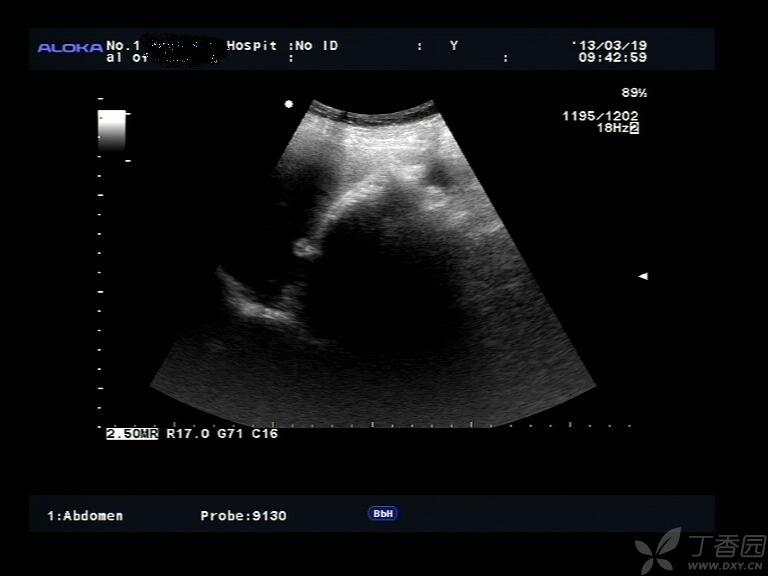

图2,IVU:

img

X线:左肾下极肿块,边界光滑,多发点片状钙化灶,左肾下肾盏受压移位、拉长、变形,肾盂输尿管上段未受侵犯。